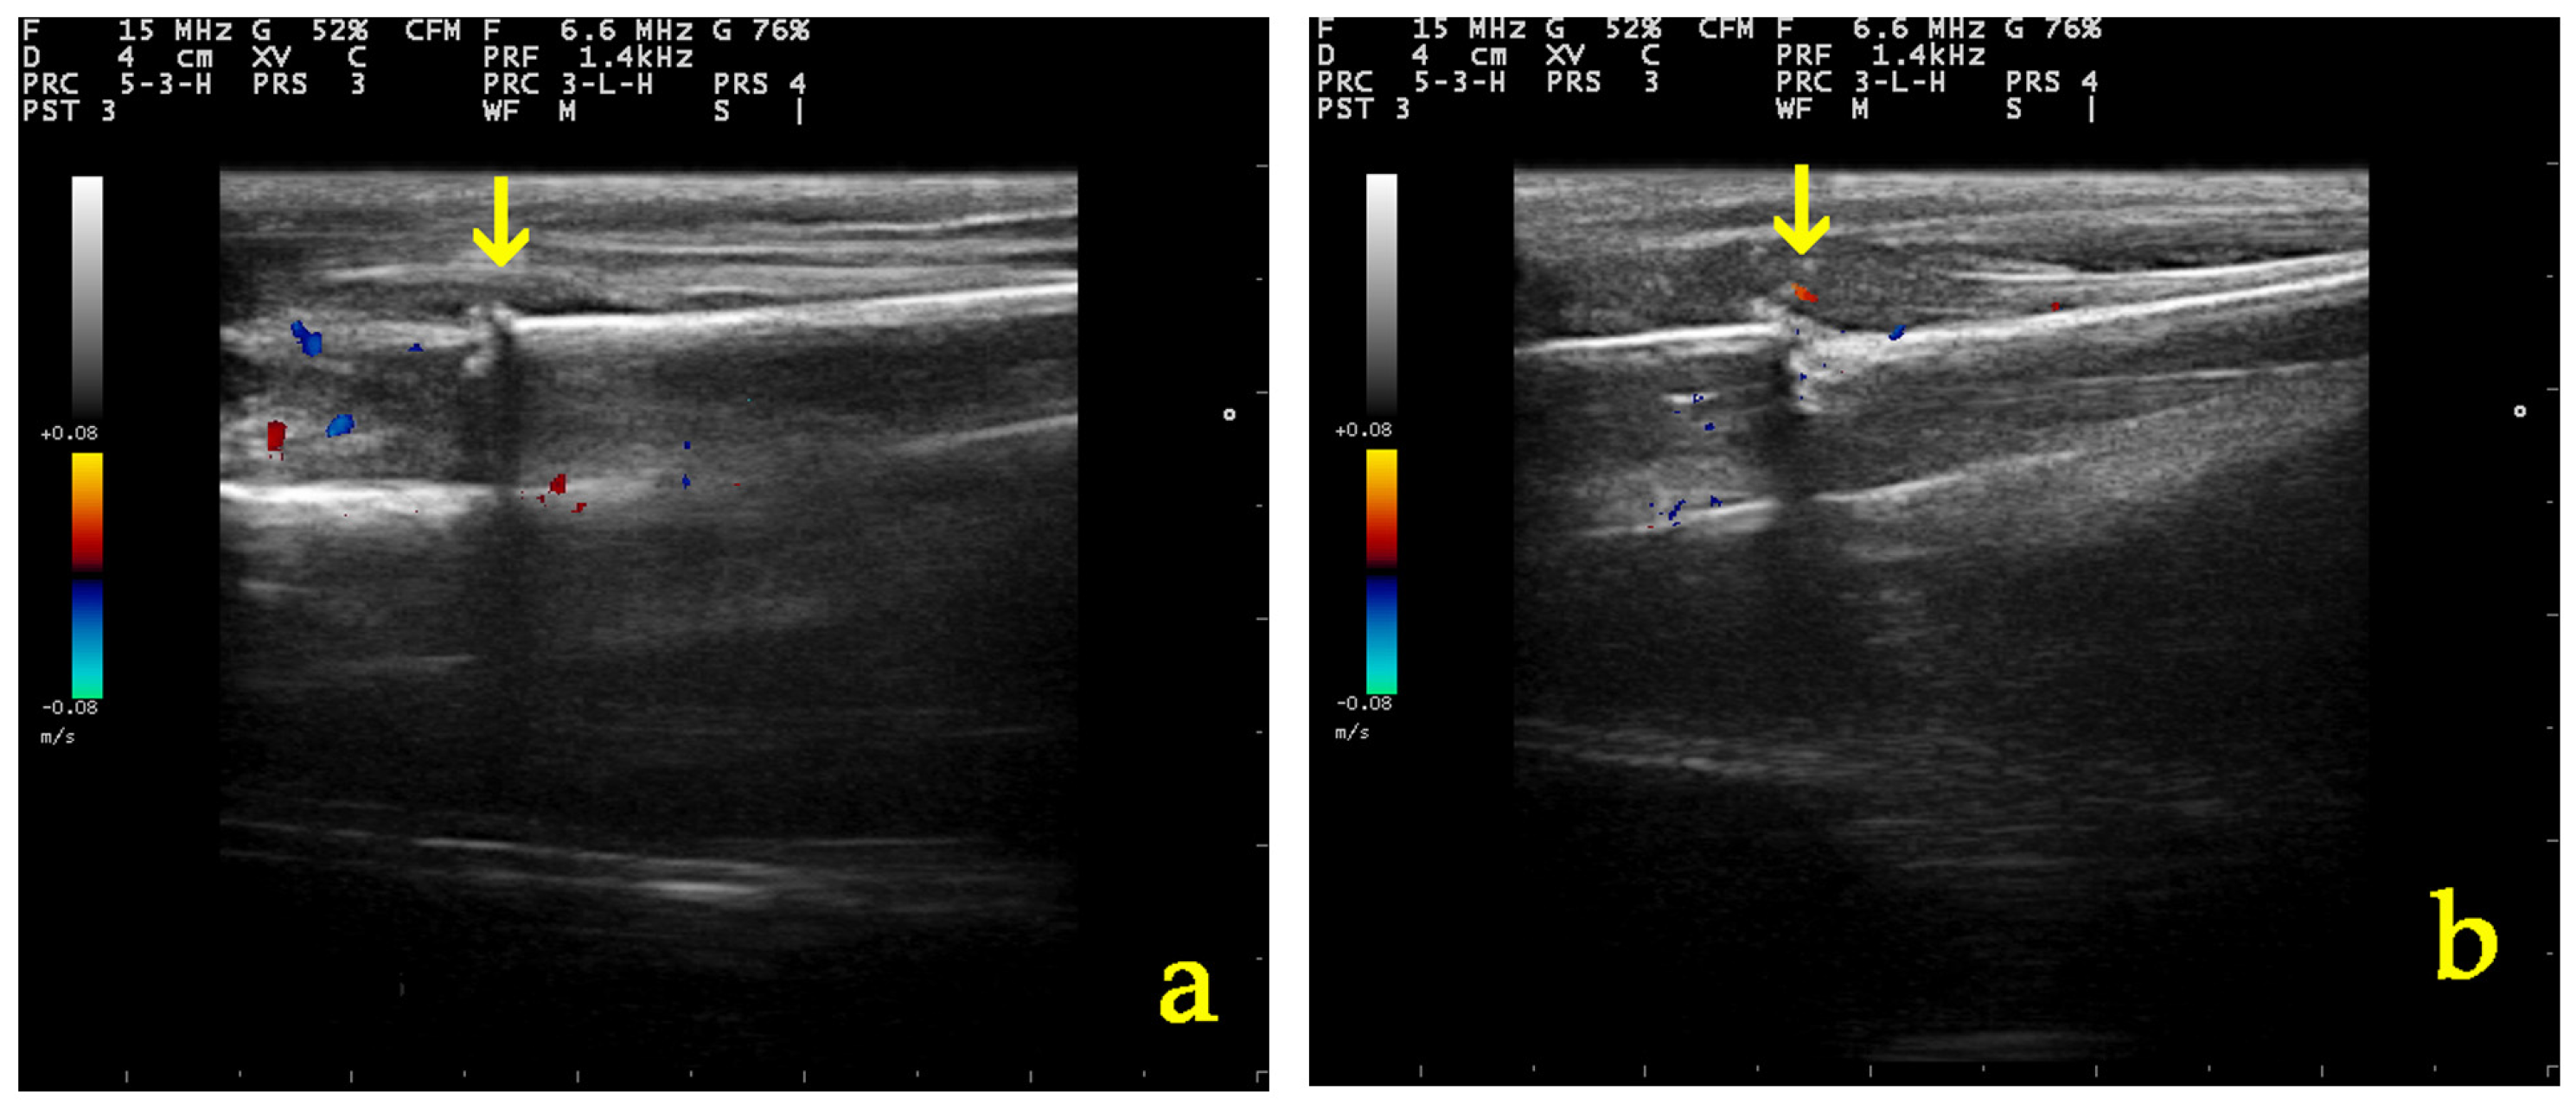

3.5.1. Ultrasonographic Examination

3.5.2. Radiographic Examination

| Parameter of Ultrasonographic Examination | Group | D0 | D5 | D10 | D20 | D28 |

|---|---|---|---|---|---|---|

| Echogenicity and structural organization of the tissue at the fracture site | A | 1 (1–1) | 2 (1–2) | 2 (2–2) | 3 (3–4) | 3.5 (3–4) |

| B | 1 (1–1) | 1 (1–2) | 2 (2–2) | 3 (2–4) | 4 (2–4) | |

| Formation of the callus and the vascularization present at the osteotomy | A | 1 (1–1) | 2 (2–2) | 2 (2–2) | 3 (2–4) | 3.5 (3–4) |

| B | 1 (1–1) | 2 (2–2) | 2 (1–2) | 3 (2–4) | 4 (2–4) | |

| Total grade | A | 1 (1–1) | 1.5 (1–2) | 2 (2–2) | 3 (3–4) | 3.5 (3–4) |

| B | 1 (1–1) | 1 (1–2) | 2 (2–2) | 3 (2–4) | 4 (2–4) |